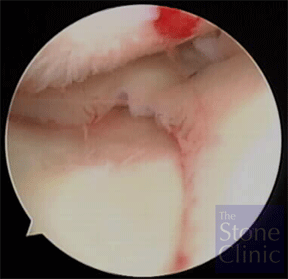

This next photo on the right shows the meniscal allograft in place. The meniscal allograft is the structure to the right of the photo. Above it is the rounded end of the femur and below is the flattened top of the tibia - the tibial plateau.